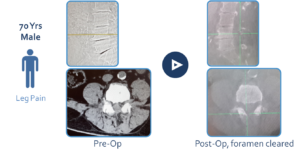

case-5-lumbar-70-male-leg-pain